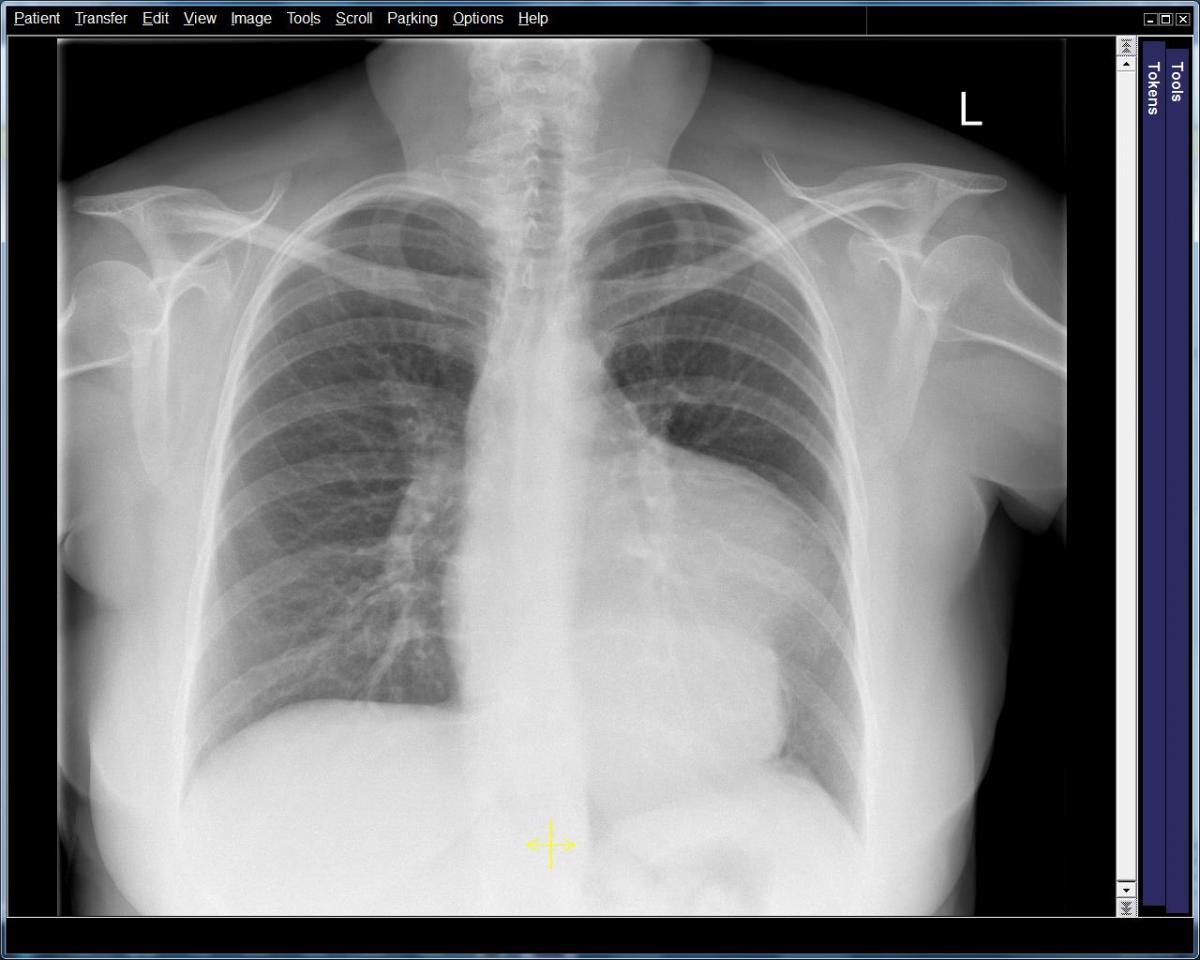

Figure 1: PA Chest radiograph revealing a soft tissue density measuring 6.7 x 9 cm, merging with the left heart border. Most likely vascular in origin, however mediastinal masses could not be ruled out.

The patient’s neurological symptoms continued to improve with only minor residual weakness in her left arm. She began to demonstrate signs of progressive cardiac failure. Subsequent serial TTE demonstrated a progressively enlarging inferior aneurysm. Coronary angiography showed her to have an occluded right coronary artery. Chest radiography and CT scan of the thorax showed a very large aneurysmal dilatation of the left ventricle containing a moderate amount of thrombus (Figure 1). The aneurysm arose from the inferior wall of the mid cavity of the ventricle. Its neck measured approximately 40 mm. The aneurysm itself measured 110 x 90 x 120 mm. The left ventricle was dilated with thinning of the myocardium globally. In contrast, the cardiac MRI (Video 1,2) showed that the left ventricle had a ruptured inferior free wall measuring 30 x 32 mm, which opened into an inferior pseudoaneurysm measuring 60 mm deep and 99 mm across, with a significant layer of thrombus.